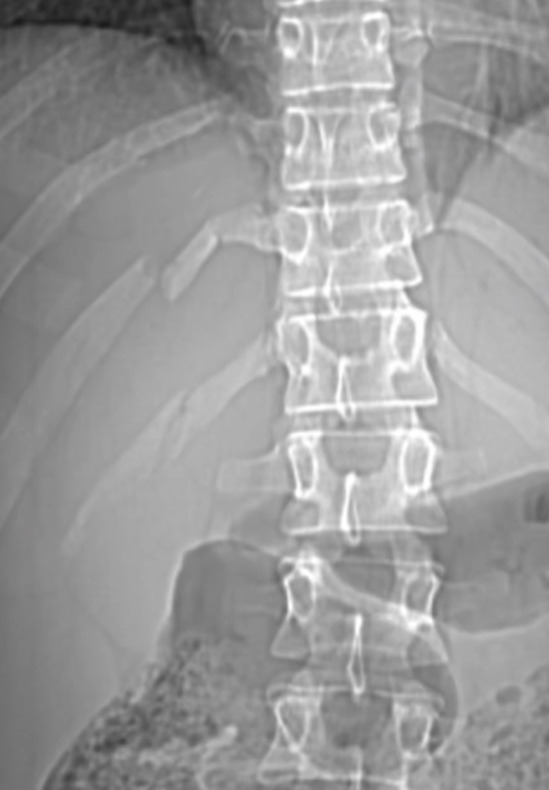

Doctors confirmed the 30-year-old broke three ribs in the accident, as reported by Need To Know.

She said: “I’m writing to you from my bed on complete rest, babes, resting so my three broken ribs heal as soon as possible.